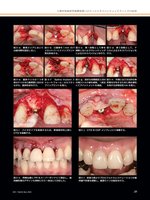

39上顎中切歯狭窄歯槽堤部へのリッジエキスパンジョンテクニックの応用─Vol.22,No.1,2015039図8-a 審美エリアにおいては縦切開を設定しない。図8-i バイオタイプを変換するため、骨補填材料上部にCTGを設置する。図8-j CTGをCGFメンブレンにて被覆する。図8-k 両隣在歯にPRをスーパーボンドにて固定し、歯肉縁形態のデザインも同時に行う1回法にて対応した。図8-l 術後12週よりプロビジョナルレストレーションの歯肉縁下形態を調整し、歯頚ラインの設定を行う。図8-b 口蓋骨を1mm のパイロットバーにてインプラント窩を形成する。図8-c 第1段階として骨を削除しないようマレッティングによるエキスパンジョンを行う。図8-d 第2段階として、ドリルによるエキスパンジョンを行う。図8-e 最終ドリルの1つ手前のドリルを口蓋骨壁に沿わせながら、最終形成を行う。図8-f Spline Implantストレートフォーム・セルフタップインプラントを埋入。図8-g 良好な初期固定と35Nの埋入トルク値を確保。1回法にてアバットメントを連結。図8-h 外側には三次元的な骨形態を付与するために骨伝導性を有する非吸収性HAを填入。